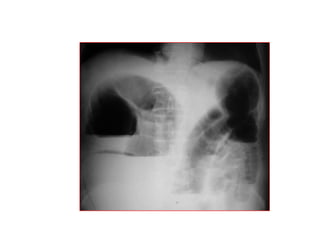

THUÛNG TAÏNG ROÃNG

* Vò trí

o Thöôøng ôû phaàn cao oáng tieâu hoaù (vieâm loeùt, nhieãm truøng,

thuûng do ngoaïi vaät nuoát vaøo…)

o Caùc oáng tieâu hoaù tröôùc coät soáng (chaán thöông)

* Daáu hieäu kinh ñieån: lieàm hôi döôùi hoaønh: xuaát hieän 6-8

giôø sau thuûng vôùi löôïng hôi khoaûng 20-50ml

* Caùc tö theá khaùc: BN nghieâng (T) laáy heát bôø ngoaøi gan vaø

hoá chaäu (P), naèm ngöõa tia phoùng ngang…